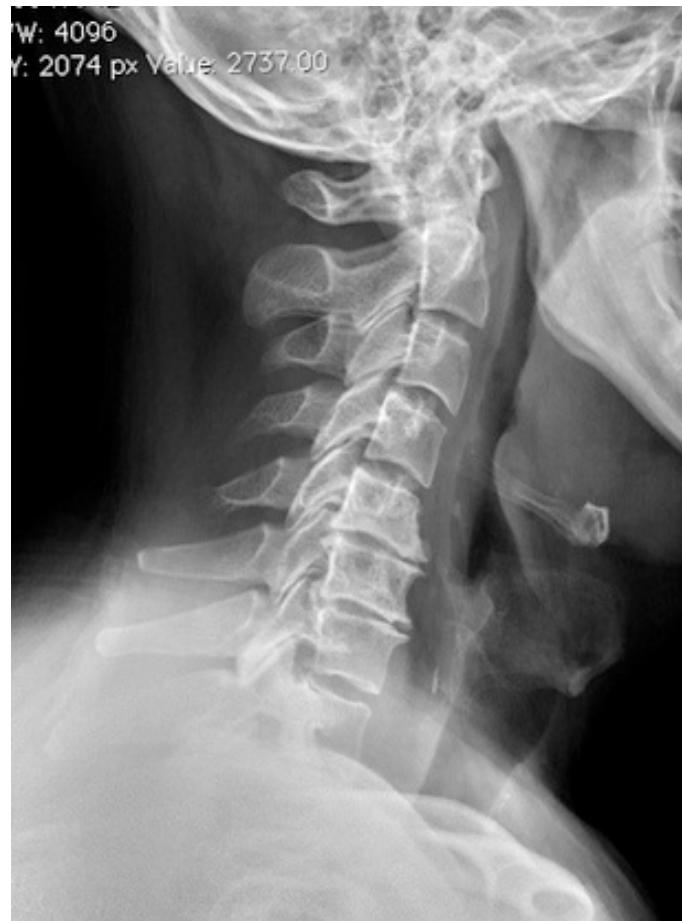

Cervical Spondylosis

- Pathophysiology: Natural aging and degenerative process of cervical motion segment

- Age of onset: Typically begins at age 40-50; 85% of patients >65 years

- Presentation: Can lead to cervical radiculopathy, cervical myelopathy, or axial neck pain

- Diagnosis: Plain radiographs of cervical spine

- Treatment: Observation, medical management, or surgical management depending on severity and chronicity of pain, presence of instability, or neurological deficits

Cervical Myelopathy Z

- Definition: Common form of neurologic impairment caused by compression of cervical spinal cord, most commonly due to degenerative cervical spondylosis

- Typical presentation: Older patients with symmetric numbness and tingling in extremities, hand clumsiness, and gait imbalance

- Treatment: Usually surgical decompression and stabilization as condition is associated with step-wise progression

Imaging:

- MRI: Study of choice to evaluate degree of spinal cord and nerve root compression

Cervical Radiculopathy

- Definition: Clinical condition characterized by unilateral arm pain, numbness and tingling in dermatomal distribution in hand, and weakness in specific muscle groups

- Evaluation: Thorough neurologic examination, cervical spine radiographs including flexion-extension views, and MRI of cervical spine

- Treatment: Nonoperative treatment successful in 75%-90% of patients; surgical decompression reserved for refractory cases or patients with progressive neurologic deficits

Imaging Examples:

Surgical Treatment - Anterior Cervical Discectomy and Fusion: